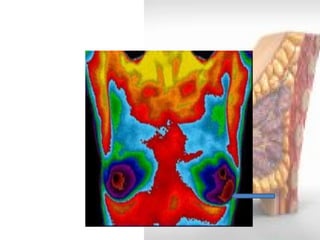

Thermography

•Transmission of detectable heat from the breast is nonspecific, and in malignant lesions results from the hypervascularity that frequently accompanies carcinoma.

•Three thermographic methods are used: telethermography, contact thermography, and computed tomography.

•Using special heat scanners it is possible to delineate these “hot” perfusion sites on film.

• Results are variable and inaccurate, Sensitivity is less than 50 percent and it is not advocated as a routine screening method, because it is unable to detect minimal breast cancer.